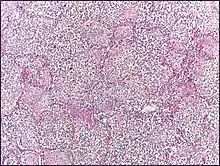

Micrograph of lobar pneumonia, H&E stain.

Lobar pneumonia usually has an acute progression. Classically, the disease has four stages:[1]

• Congestion in the first 24 hours: This stage is characterized histologically by vascular engorgement, intra-alveolar fluid, small numbers of neutrophils, often numerous bacteria. Grossly, the lung is heavy and hyperemic.

• Red hepatization or consolidation: Vascular congestion persists, with extravasation of red blood cells into alveolar spaces, along with increased numbers of neutrophils and fibrin. The filling of airspaces by the exudate leads to a gross appearance of solidification, or consolidation, of the alveolar parenchyma. This appearance has been likened to that of the liver, hence the term "hepatization".

• Grey hepatization: Red blood cells disintegrate, with persistence of the neutrophils and fibrin. The alveoli still appear consolidated, but grossly the color is paler and the cut surface is drier. This is when death typically occurs in severe cases.

• Resolution (complete recovery): The exudate is digested by enzymatic activity, and cleared by macrophages or by cough mechanism. Enzymes produced by neutrophils will liquify exudates, and this will either be coughed up in sputum or be drained via lymph.